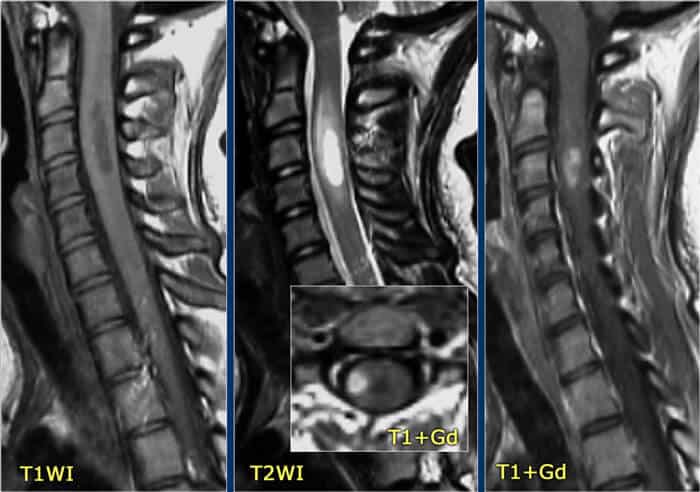

- Radiology scan from MRI or CT – Computed tomography (CT) & Magnetic resonance imaging (MRI) scans are used to detect inflammation. Radiology scans help create a three-dimensional (cross-sectional) view/image of areas in the body, including the spinal cord and brain. An MRI of the spine can confirm any lesions in the spinal cord, while a brain CT scan can be used to provide signs of other potential causes. If none of the methods lead to a specific cause, the patient is often diagnosed with idiopathic transverse myelitis.

The overall success and efficacy of MSC+ stem cell treatment are measured by reducing relapse rate and the total number of lesions 6-12 months after MSC+ treatment. The secondary outcome is achieved by accelerating recovery time, improving overall neural function, and restoring tissue. Improvements are measured using follow exams and radiology scans post-MSC+ Therapy.